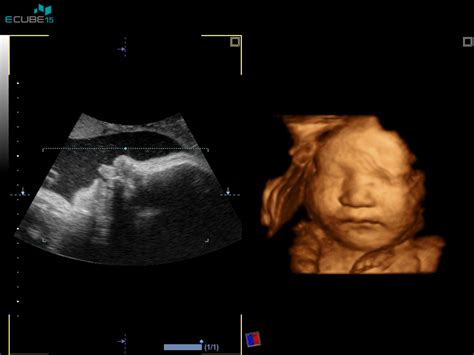

V 70. in 80. letih 20. stoletja se je začela razvijati medicina plodu (fetalna medicina) in tako v zadnjih desetletjih spremljamo tudi rast plodu. Zastoj v rasti plodu pomeni, da je ocenjena velikost plodu manjša, kot bi pričakovali glede na višino nosečnosti. Rast ocenjujemo z ultrazvokom (UZ) in ultrazvočne meritve vnašamo v krivulje rasti ter tako sledimo rasti plodu.

Še nikoli viden pogled na človeško življenje v maternici | Dojenčica Olivia